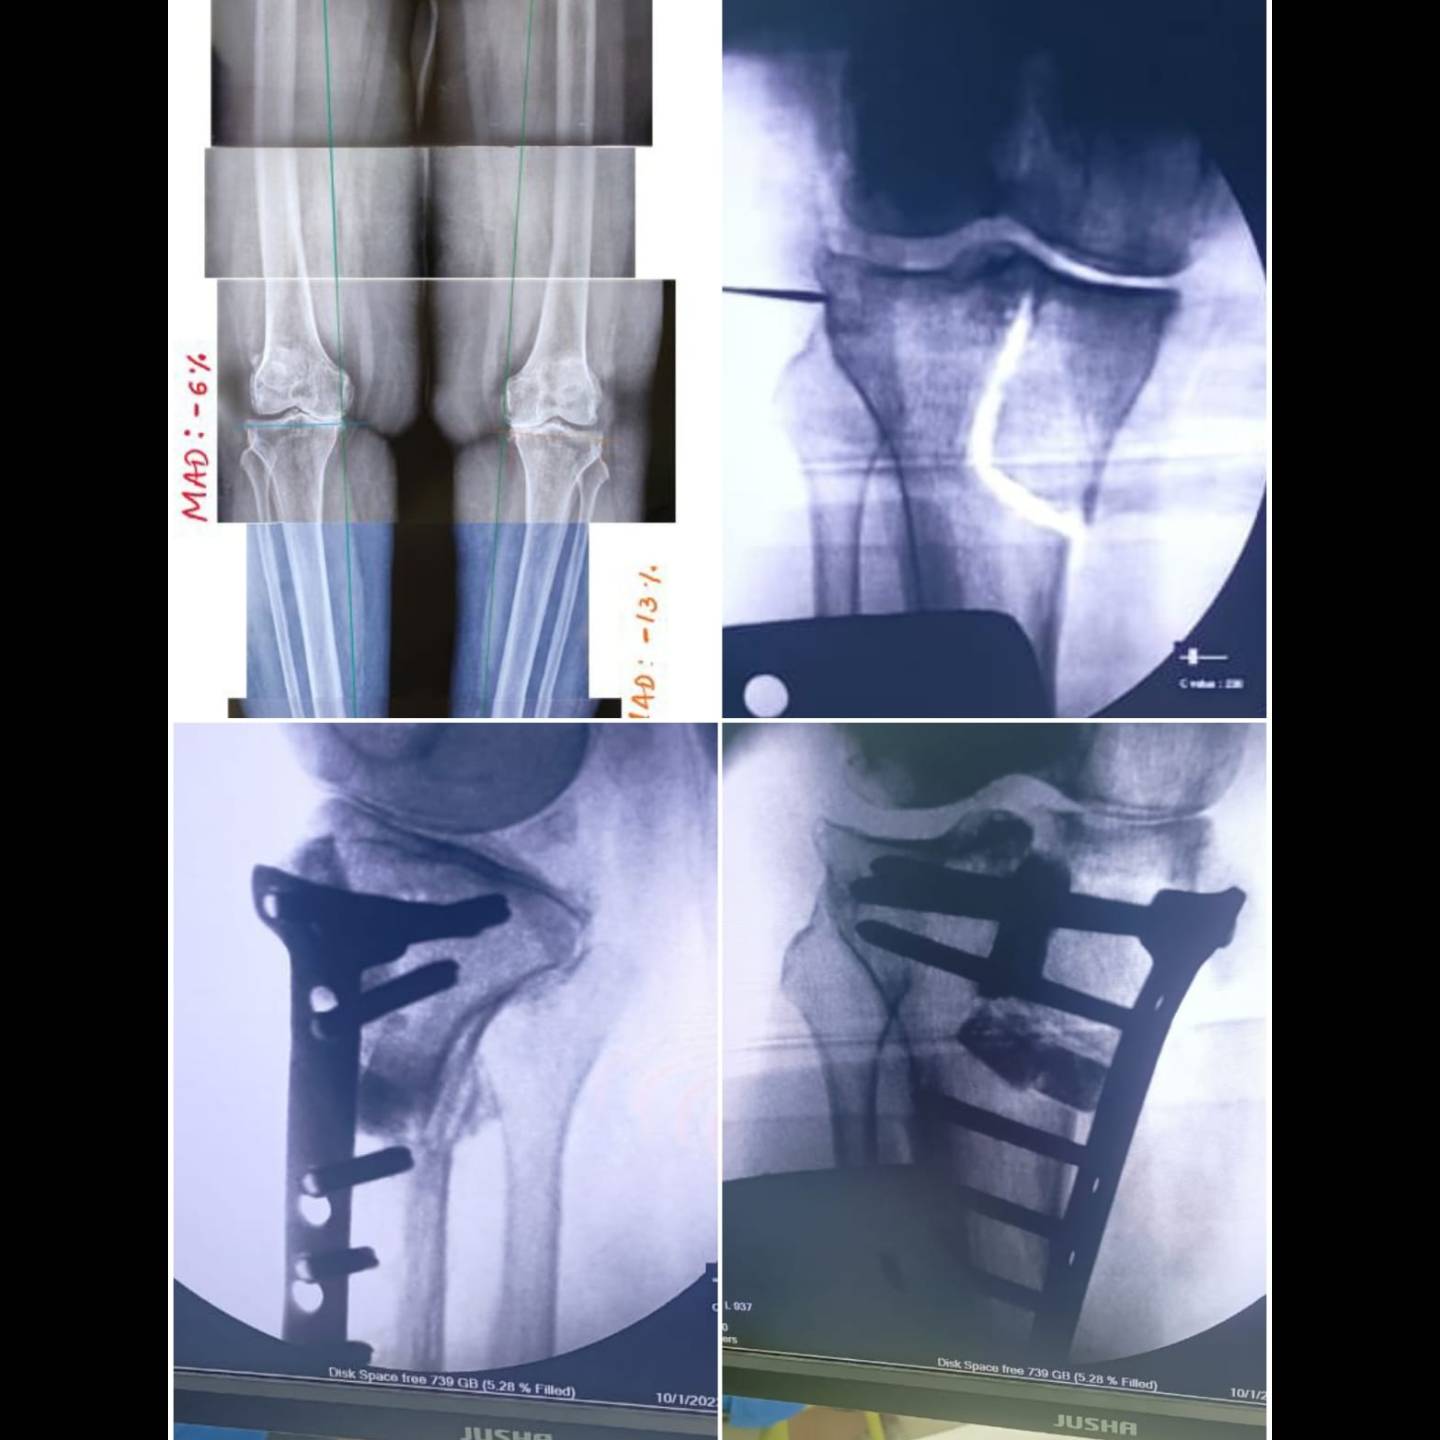

Tibial condylar valgus osteotomy for arthritic knee.

15 y old young girl with severe bow leg deformity.. ilizarov deformity correction.

45y young female with severe bow leg deformity... ilizarov deformity correction.

young female with knock knees..distal femur deformity correction.

Young female ...with knock knees..before and after complete correction of her deformity.